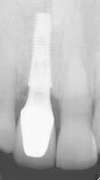

Voici la radiographie de contrôle :

Ce traitement est extrêmement fiable et permet une esthétique optimale. On peut observer lorsque la patiente sourit et en très gros plan, une parfaite ostéointégration de la prothèse.